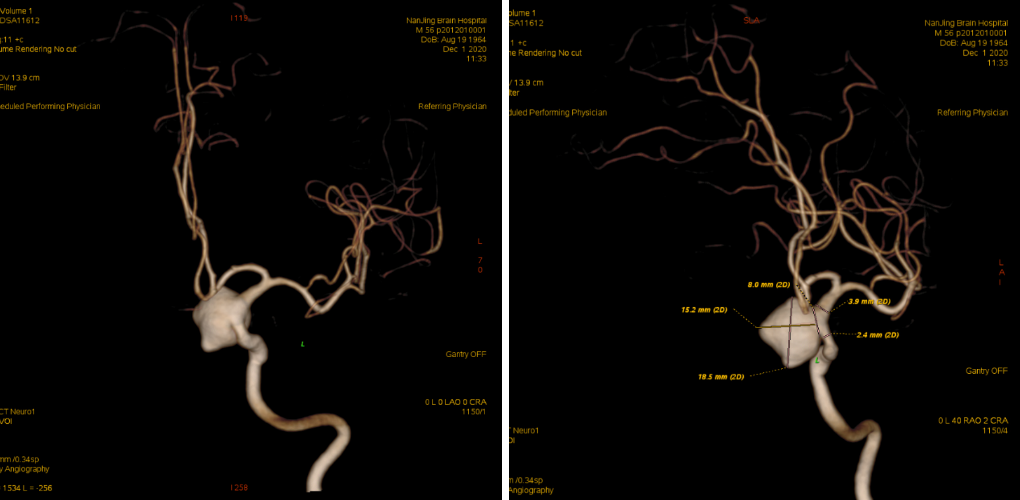

入院后予完善头颅DSA检查提示左侧颈内动脉眼动脉段动脉瘤;头颅MR提示脑内多发陈旧梗死,告知其介入栓塞、开颅夹闭等治疗方式、利弊、风险及费用等,患方商量后决定行开颅动脉瘤夹闭术。

头颈部CTA

术前DSA

入院后予完善MRI及头颅DSA检查提示右侧颈内动脉眼动脉段动脉瘤;告知其介入栓塞、开颅夹闭等治疗方式、利弊、风险及费用等,患方商量后决定行开颅动脉瘤夹闭术。

科内讨论后认为:患者颈内动脉床突旁大动脉瘤诊断明确,患者动脉瘤破裂出血,需急诊手术治疗。术中应先在颈部暴露颈内动脉。采用Dolenc入路硬膜外磨除前床突及视神经管。术中注意保护好眼动脉。暴露动脉瘤后可孤立动脉瘤,并在颈部穿刺颈动脉并逆向抽吸,降低动脉瘤的张力后塑形夹闭动脉瘤。